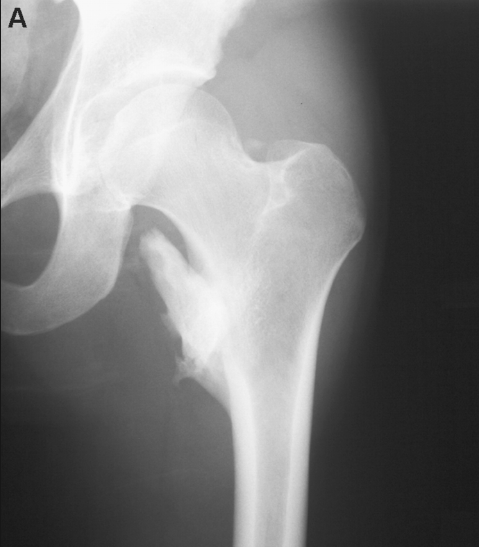

Một người đàn ông 28 tuổi bị tổn thương tuỷ sống hoàn toàn ngang mức T8 sau một tai nạn xe máy. Năm tuần sau khi nhập vào đơn vị chấn thương cột sống, bệnh nhân than đau ở háng trái. Trên lâm sàng, toàn bộ chân trái bị sưng và đau, sờ thấy háng nóng và đau, đau nhiều khi vận động thụ động. Kết quả X quang thẳng cho thấy dấu hiệu canxi hoá mô mềm gần với mặt khớp háng trái.

Các xét nghiệm thường bình thường ngoại trừ tăng phosphatase kiềm, tốc độ máu lắng và protein phản ứng C, thường là tăng vừa một vài tuần sau khi khởi phát và là các chỉ báo tốt cho hoạt tính của bệnh. Chụp X quang thường có giá trị chẩn đoán trong các trường hợp rõ ràng. Trong cốt hoá lạc chổ nhẹ và sớm, scan xương ba pha là một công cụ có giá trị để xác định cốt hoá và xét nghiệm này cũng có thể đánh giá sự trưởng thành trong bệnh tiến triển. CT và MRI có vai trò, đặc biệt là để đánh giá trước phẫu thuật để kiểm tra mức độ (lan rộng) của cốt hoá lạc chổ và liên quan với các mạch máu. CT cũng có thể giúp loại trừ các bệnh lý khác như tụ máu hoặc khối u bị vôi hóa.